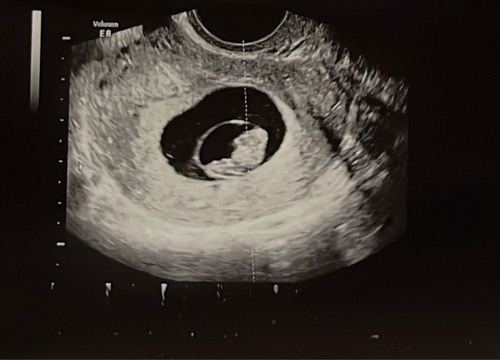

Dit was met de eerste echo 7+3 inwendig. Wat zou deze theorie dan betekenen?

Benieuwd of dit klopt ik zal het rond 1 oktober pas weten. Maar ik las wel dat je een echo tussen 6-7 weken moet hebben wil je deze theorie toepassen